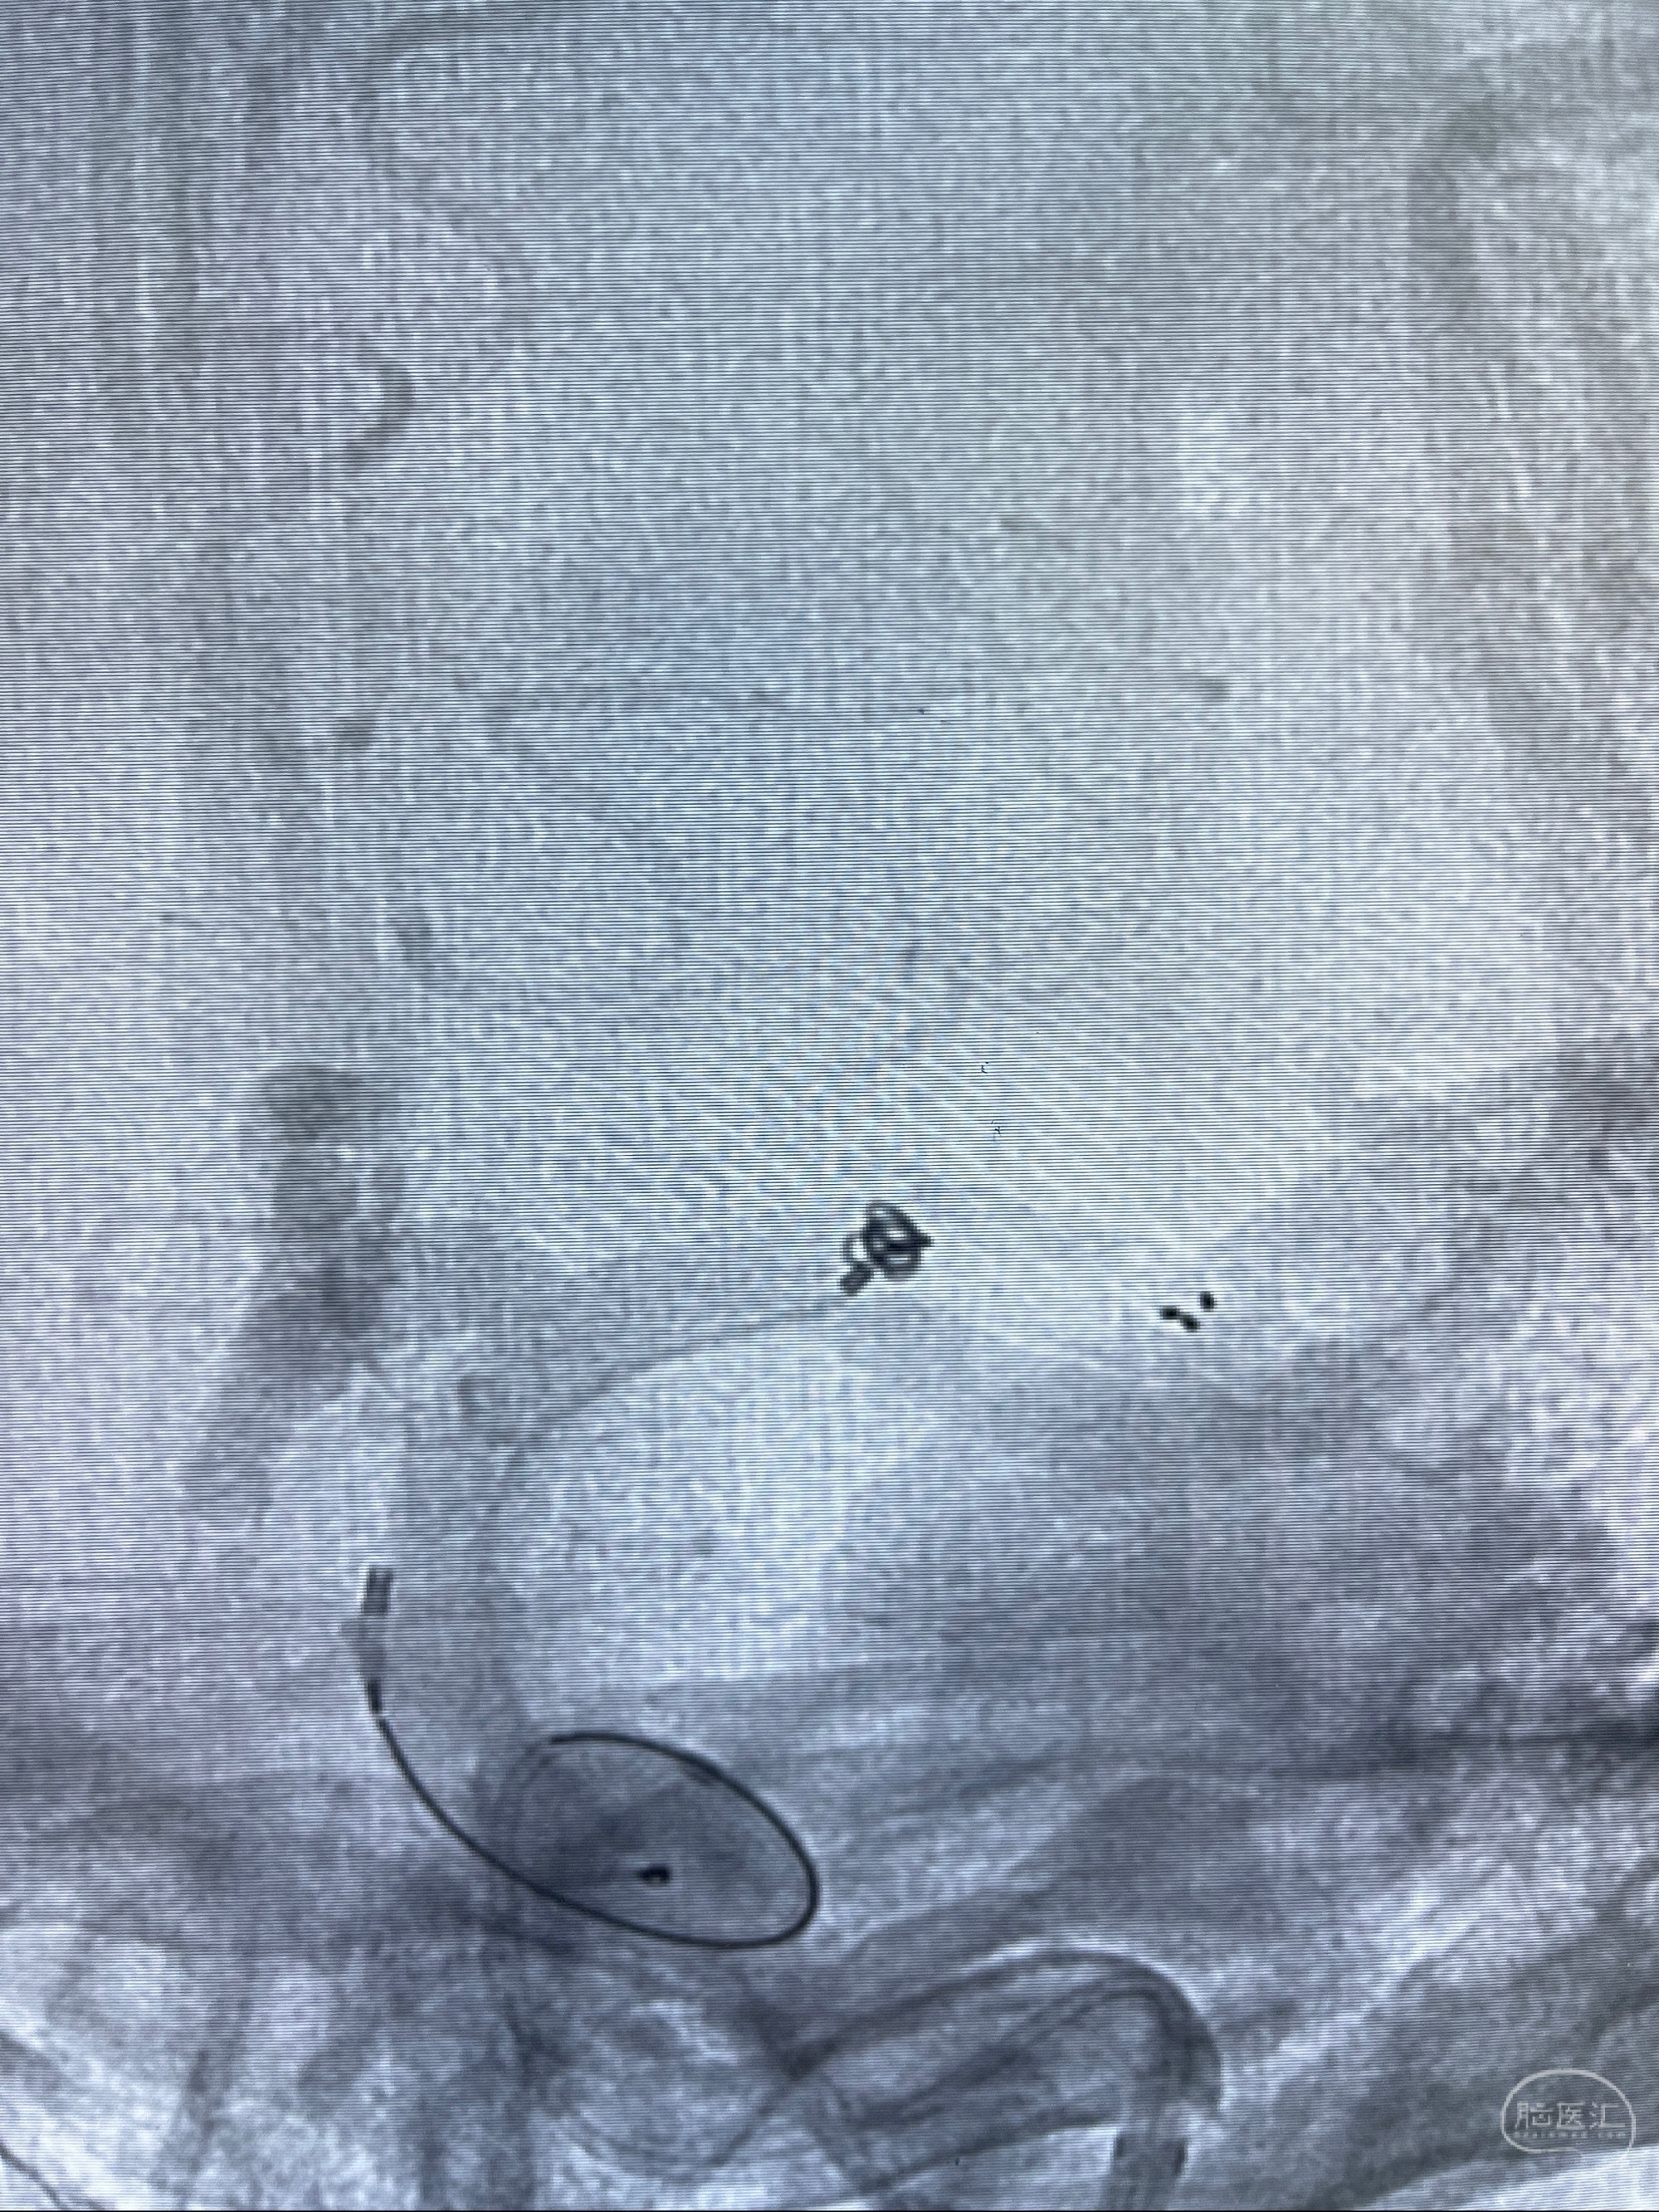

2023-08-14DSA:

左侧大脑中动脉动脉瘤,约2.6-2.8-3.4-2mm大小(瘤颈部、瘤体部、瘤高)

1.左侧大脑中动脉动脉瘤,约2.6-2.8-3.4-2mm大小(瘤颈部、瘤体部、瘤高)

2.外科手术夹闭or介入支架辅助栓塞